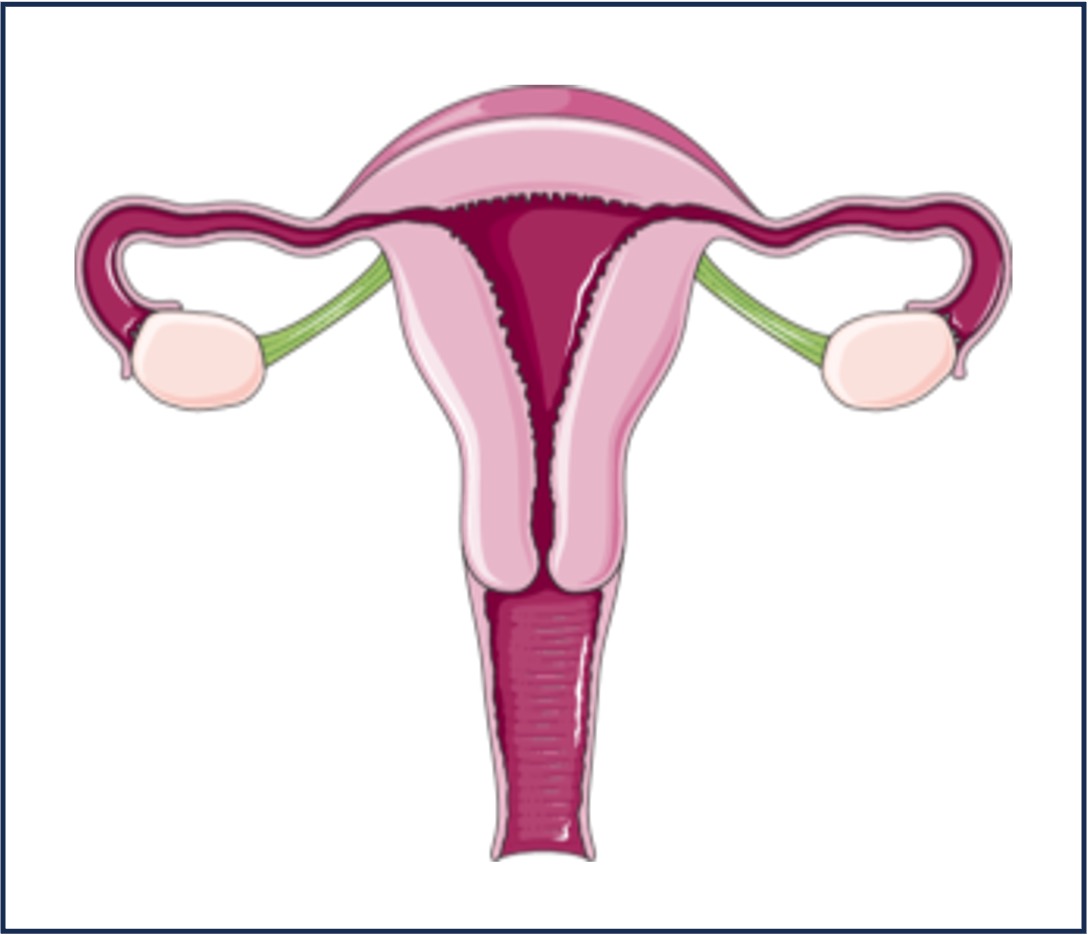

Females:

-

FSH acts on the ovaries to trigger follicle development and the production of oestrogen, while LH is responsible for ovulation and the subsequent release of progesterone

-

Oestrogen and progesterone are the sex hormones (steroids) that promote the development of the secondary sex characteristics in females

-

These secondary sex characteristics include the formation of body hair and breast development

-